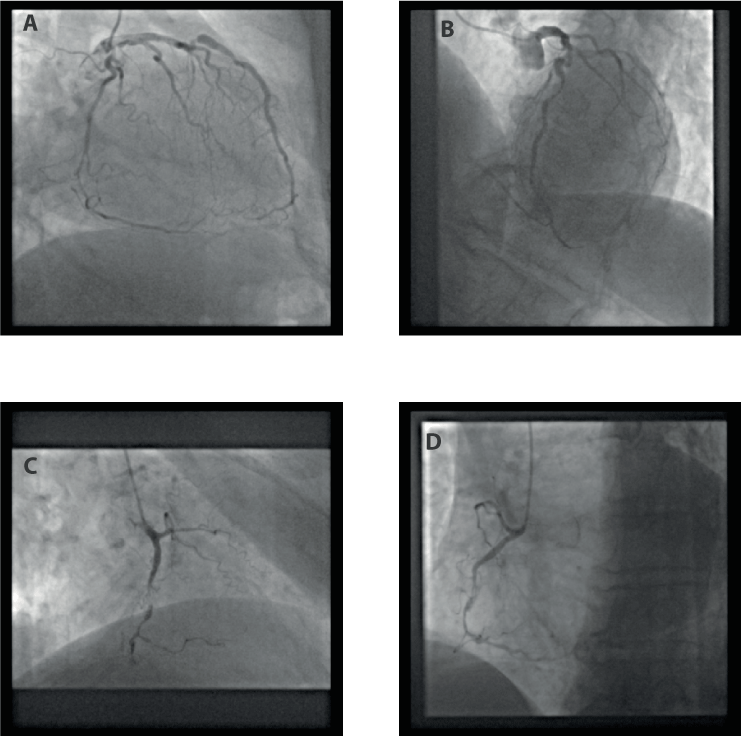

Figure 1. Coronary angiography (16.01.2020). A + B: left coronary artery. Note the retrograde filling of the distal right coronary artery. C + D: right coronary artery.

Figure 2. Percutaneous coronary intervention of right coronary artery (RCA) with implantation of 3 drug-eluting stents (31.01.2020). A + B: before PCI (simultaneous injection into left and right coronary artery). C + D: RCA after PCI.